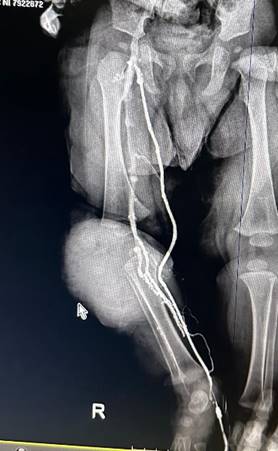

Se practica ecografía Doppler en modo B, con transductor lineal, a través del cual se detecta abundante contenido hemático en compartimiento anterior y lateral de la pierna, con imagen característica de quistes multitabicados Figura B, además se realiza una flebografía ascendente en la cual se evidencia que no existen fistulas arteriovenosas Figura C. En la Angiotac se descarta dependencia o comunicación con grandes vasos Figura D, por tanto, se diagnostica Malformación Vascular: Linfangioma.

Figura C. Flebografía Ascendente de Pierna Derecha en la cual se descarta malformación arteriovenosa de alto flujo.